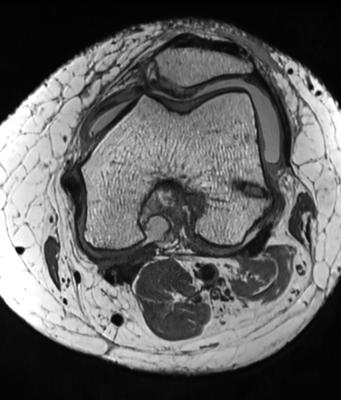

AIRS Medical's product SwiftMR enhances the quality of MRI images through fine-tuned deep learning technology. SwiftMR can reduce MRI scan times by up to 50% while enhancing image quality using AI-powered denoising and sharpening. FONAR, founded in 1978, introduced the first commercial MRI scanner in 1980. Today its signature product is the 0.6T UPRIGHT MRI. The FONAR UPRIGHT acquires MR images in an open magnet that accommodates a wide variety of static and dynamic patient postures, including sitting; standing; upright flexion, extension, lateral bending, and rotation; as well as recumbent.

Through this partnership with FONAR, AIRS Medical has expanded the application of SwiftMR beyond 1.5T and 3.0T MRIs to include lower-field MRI scanners, securing access to an expanded market segment. Kevin Yang, Head of AIRS Medical's U.S. Operations & Clinical Research said, "AIRS Medical looks forward to the strategic partnership with FONAR. The combined efforts of both parties will accelerate our growth and strengthen our North American business capabilities. We expect that this agreement, leveraging FONAR's 45 years of expertise and capabilities, will bolster various aspects of our business operations in the U.S. market for SwiftMR, including sales, marketing, and even research collaborations."

Under the slogan "Breaking the common belief of MRI through AI," AIRS Medical will showcase a range of cutting-edge AI healthcare technologies and advancements at RSNA 2023. A noteworthy development this year is clearance from the US FDA to expand the application of SwiftMR to all body parts, all pulse sequences, and all scanner models with 0.25T, 0.6T, 1.5T, and 3.0T.

In addition, AIRS Medical will showcase two accepted research abstracts and host two AI Theater Presentations. Yangsean Choi, MD, will discuss clinical applications and on-going research using SwiftMR in neuroradiology. John Greenhalgh, Ph.D., Vice President of Research and Development at FONAR Corporation, will share his experience successfully implementing SwiftMR in FONAR's UPRIGHT® MRI systems. Both talks will be held at the RSNA AI Theater. Details can be found here. Please be sure to visit us at RSNA Booth #4552.